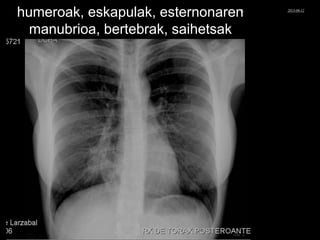

3 Hezurrak

PA LATERALA

Humeroak

Eskapulak

Esternoia manubrioa

Bertebrak

Saihetsak

Eskapula

Gorputza

Gorputza bertebralak

© Xabier Zupiria, Andoni Bueno2013-06-12

humeroak, eskapulak, esternonaren

manubrioa, bertebrak, saihetsak